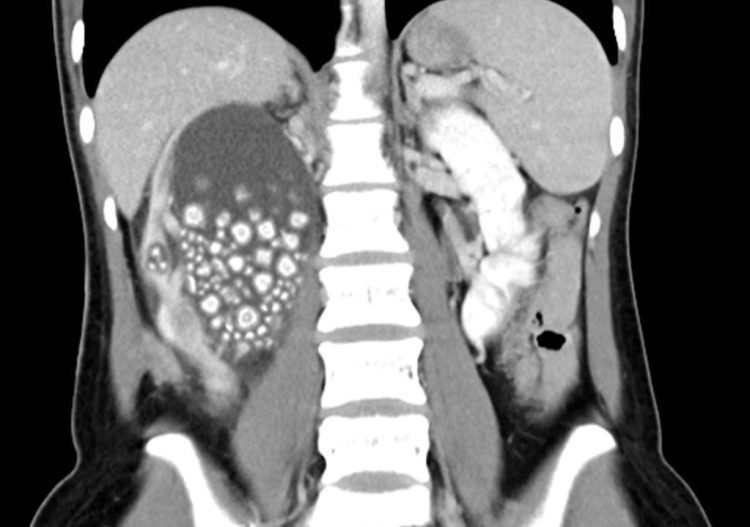

Μια 20χρονη γυναίκα από την Ταϊβάν υποβλήθηκε πρόσφατα σε χειρουργική επέμβαση για την αφαίρεση όχι λιγότερων από 300 μικρών λίθων από το δεξί της νεφρό.

Η 20χρονη εισήχθη σε νοσοκομείο της πόλης Taina, αφού παραπονέθηκε για έντονο πόνο στο κάτω μέρος της πλάτης της. Είχε επίσης πυρετό και μια εξέταση αίματος έδειξε ασυνήθιστα υψηλό αριθμό λευκών αιμοσφαιρίων. Οι γιατροί διέταξαν αξονική τομογραφία η οποία έδειξε ότι το δεξί νεφρό της Yu γεμάτο πέτρες. Αν και πρώτη ενέργειά τους ήταν να χορηγηθούν στη νεαρή γυναίκα αντιβιοτικά, στη συνέχεια προχώρησαν στην αφαίρεση των εκατοντάδων λίθων.

Στο τέλος, οι γιατροί κατέληξαν να αφαιρέσουν πάνω από 300 πέτρες, μεγέθους μεταξύ 5 και 2 εκατοστών. Η ασθενής τους ενημέρωσε ότι δεν έπινε σχεδόν καθόλου νερό και προτιμούσε τα ζαχαρούχα τσάγια και χυμούς για ενυδάτωση. Αυτό της προκάλεσε χρόνια αφυδάτωση